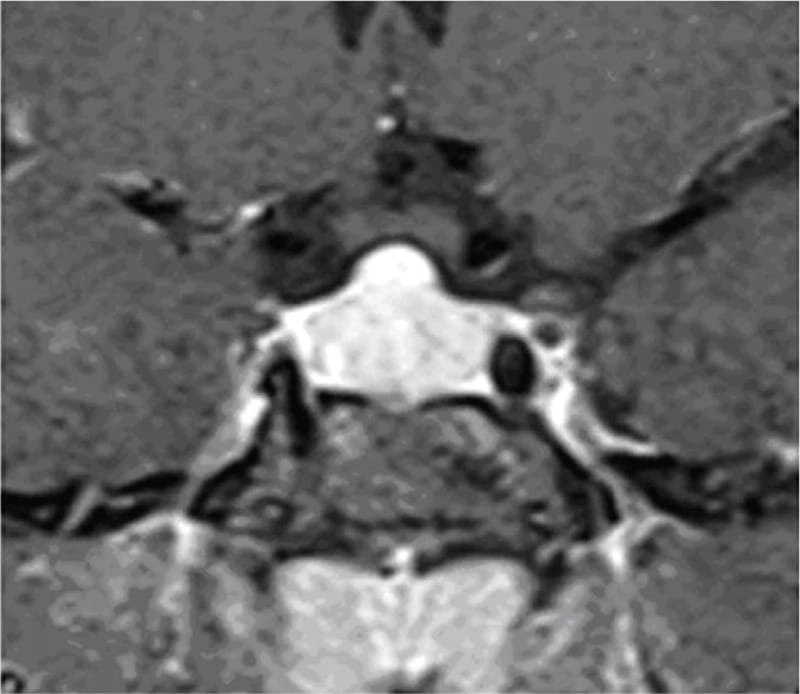

তবে পিটুইটারি হাইপারপ্লাসিয়া দেখা যায় প্রাইমারি গনাডাল, অ্যাডরিনাল বা হাইপোথাইরয়েডিজমের মত এন্ড অর্গান ইনসাফিসিয়েন্সিতে। বিশেষ করে, অব্যবহৃত প্রাইমারি হাইপোথাইরয়েডিজমে পিটুইটারি হাইপারপ্লাসিয়া পূর্বের ধারণার তুলনায় অনেক বেশি দেখা যায়। ২০১৯ সাল পর্যন্ত এরকম ১০৫টি কেস রিপোর্ট করা হয়েছে। এই ধরনের হাইপারপ্লাসিয়া গম্বুজ-আকৃতির (dome-shaped) হয়ে অপটিক কায়াজমাকে চেপে ধরতে পারে, যার ফলে অপারেশনের প্রয়োজন পড়তে পারে—যেমনটা আমাদের তৃতীয় কেসে ঘটেছিল।

কেস ২: একই রকমভাবে, ১৫ বছর বয়সী আরও একজন কিশোরী অল্প উচ্চতা ও টিউমার সন্দেহে নিউরোসার্জেনের কাছে রেফার করা হয়। তার TSH ছিল 100 এবং MRI-তে একটি ডোম-আকৃতির টিউমার দেখা যায়। যাকে ওষুধের চিকিৎসায় সত্য জীবনে ফিরিয়ে আনা হয় এবং ৬ মাসে তার উচ্চতা বৃদ্ধি পায় ও নিয়মিত মাসিক শুরু হয়। MRI-তে টিউমার সম্পূর্ণ অদৃশ্য হয়ে যায়।

চিকিৎসক তথা আবিষ্কারক সত্যম তিনটি কেসের বিষয় নিয়ে যখন তুলনা করতে নিলেন এবং পুরনো সৃষ্টি ঘাটতে শুরু করলেন তখন তিনি দেখতে পান সবগুলি ক্ষেত্রেই একই রকম সাদৃশ্য অর্থাৎ পিটুইটারি গ্রন্থি মাঝের অংশ এই গ্রন্থি দেখতে খানিকটা প্রজাপতির মতোই এবং তার মাঝের অংশের (প্রজাপতির দেহের উপরের অংশ মাথার মতই দেখতে) উপরের ভাগ সব ক্ষেত্রেই ডোমের মত বা গম্বুজ আকৃতির। তিনি এই ডোম বা গম্বুজ আকৃতি হওয়ার কারণ বিশ্লেষণ করতে গিয়ে দেখেন পিটুইটারির সামনের অংশ যেখানে থাইরোট্রপগুলো থাকে, যেখান থেকে এই টিউমারটি হয়। আর যখনই এটি বাড়বে তখন টমের মতনই তৈরি হবে। অর্থাৎ গম্বুজ আকৃতির। আর সেখান থেকেই ডোম-সাইনের উৎস অর্থাৎ আবিষ্কার।

MRI-তে এই হাইপারপ্লাসিয়া সাধারণত গম্বুজ-আকৃতির ও সমমিত হয় এবং হোমোজেনাস সিগনাল ইন্টেনসিটি দেখায়, যেখানে সাধারণ নন-ফাংশনাল পিটুইটারি অ্যাডেনোমা নানা আকার ও অসমতা নিয়ে দেখা যায়।

তাঁর দাবি, MRI-তে ‘DOME Sign’ থাকা এবং TSH বাড়তি থাকলে, সেটি হাইপোথাইরয়েডিজম-জনিত হাইপারপ্লাসিয়ার সম্ভাবনার কথা নির্দেশ করে এবং এই রোগীদের শুধুমাত্র লেভোথাইরক্সিন দিয়ে চিকিৎসা করলে পূর্ণ আরোগ্য সম্ভব।